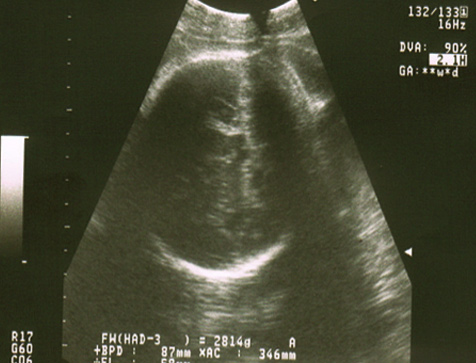

Ecografías de la semana 38 de embarazo

Ecografía semana 38: cabeza fetal. En la imagen ecográfica se observa la cabeza del bebé hacia abajo, lo que confirma la llamada presentación cefálica, ideal para el parto vaginal.